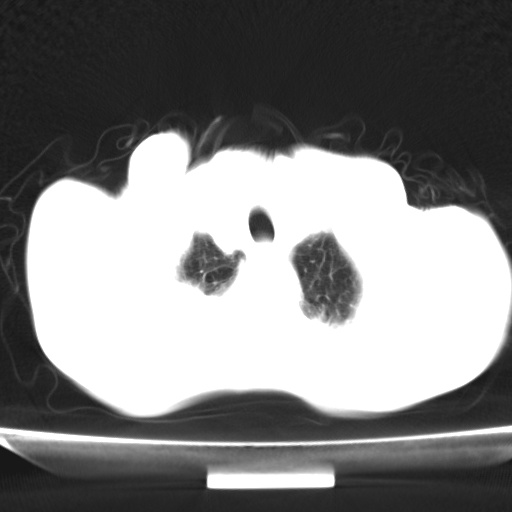

标题: CT13796:请会诊右上费病变!

患者男80岁,反复咳嗽多年,咳喘伴咯血1月

右上肺周围型肺癌伴肺门淋巴结转移.右上肺继发型肺结核.

肺结核造成的疤痕癌可能性大

右上肺结核合并右上肺癌,肺门淋巴结肿大